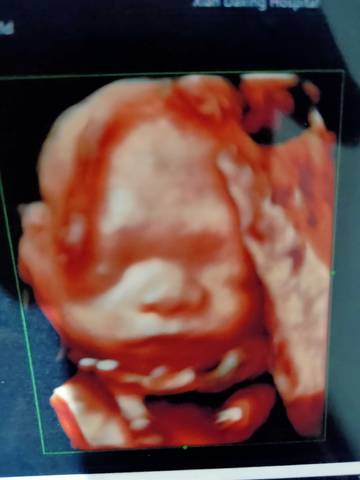

看着我的小可爱长得还挺漂亮,就是带了两圈大项链

脐带绕颈了?这会儿还小,活动空间还大。你注意胎动情况就行。